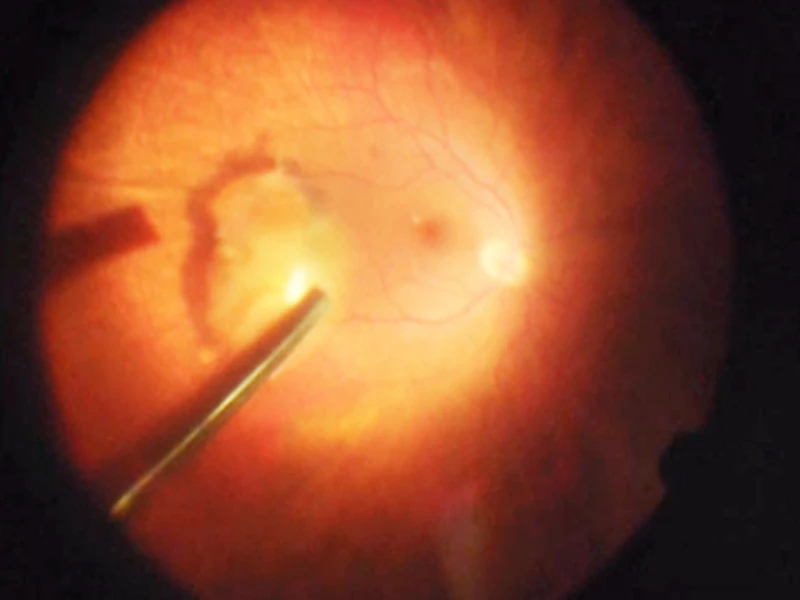

Lens sitting on the retina after falling to the back of the eye due to weak support structures (zonules), creating a blockage that prevented aqueous fluid circulation and drainage from the eye.

Lens dislocation in the left eye.